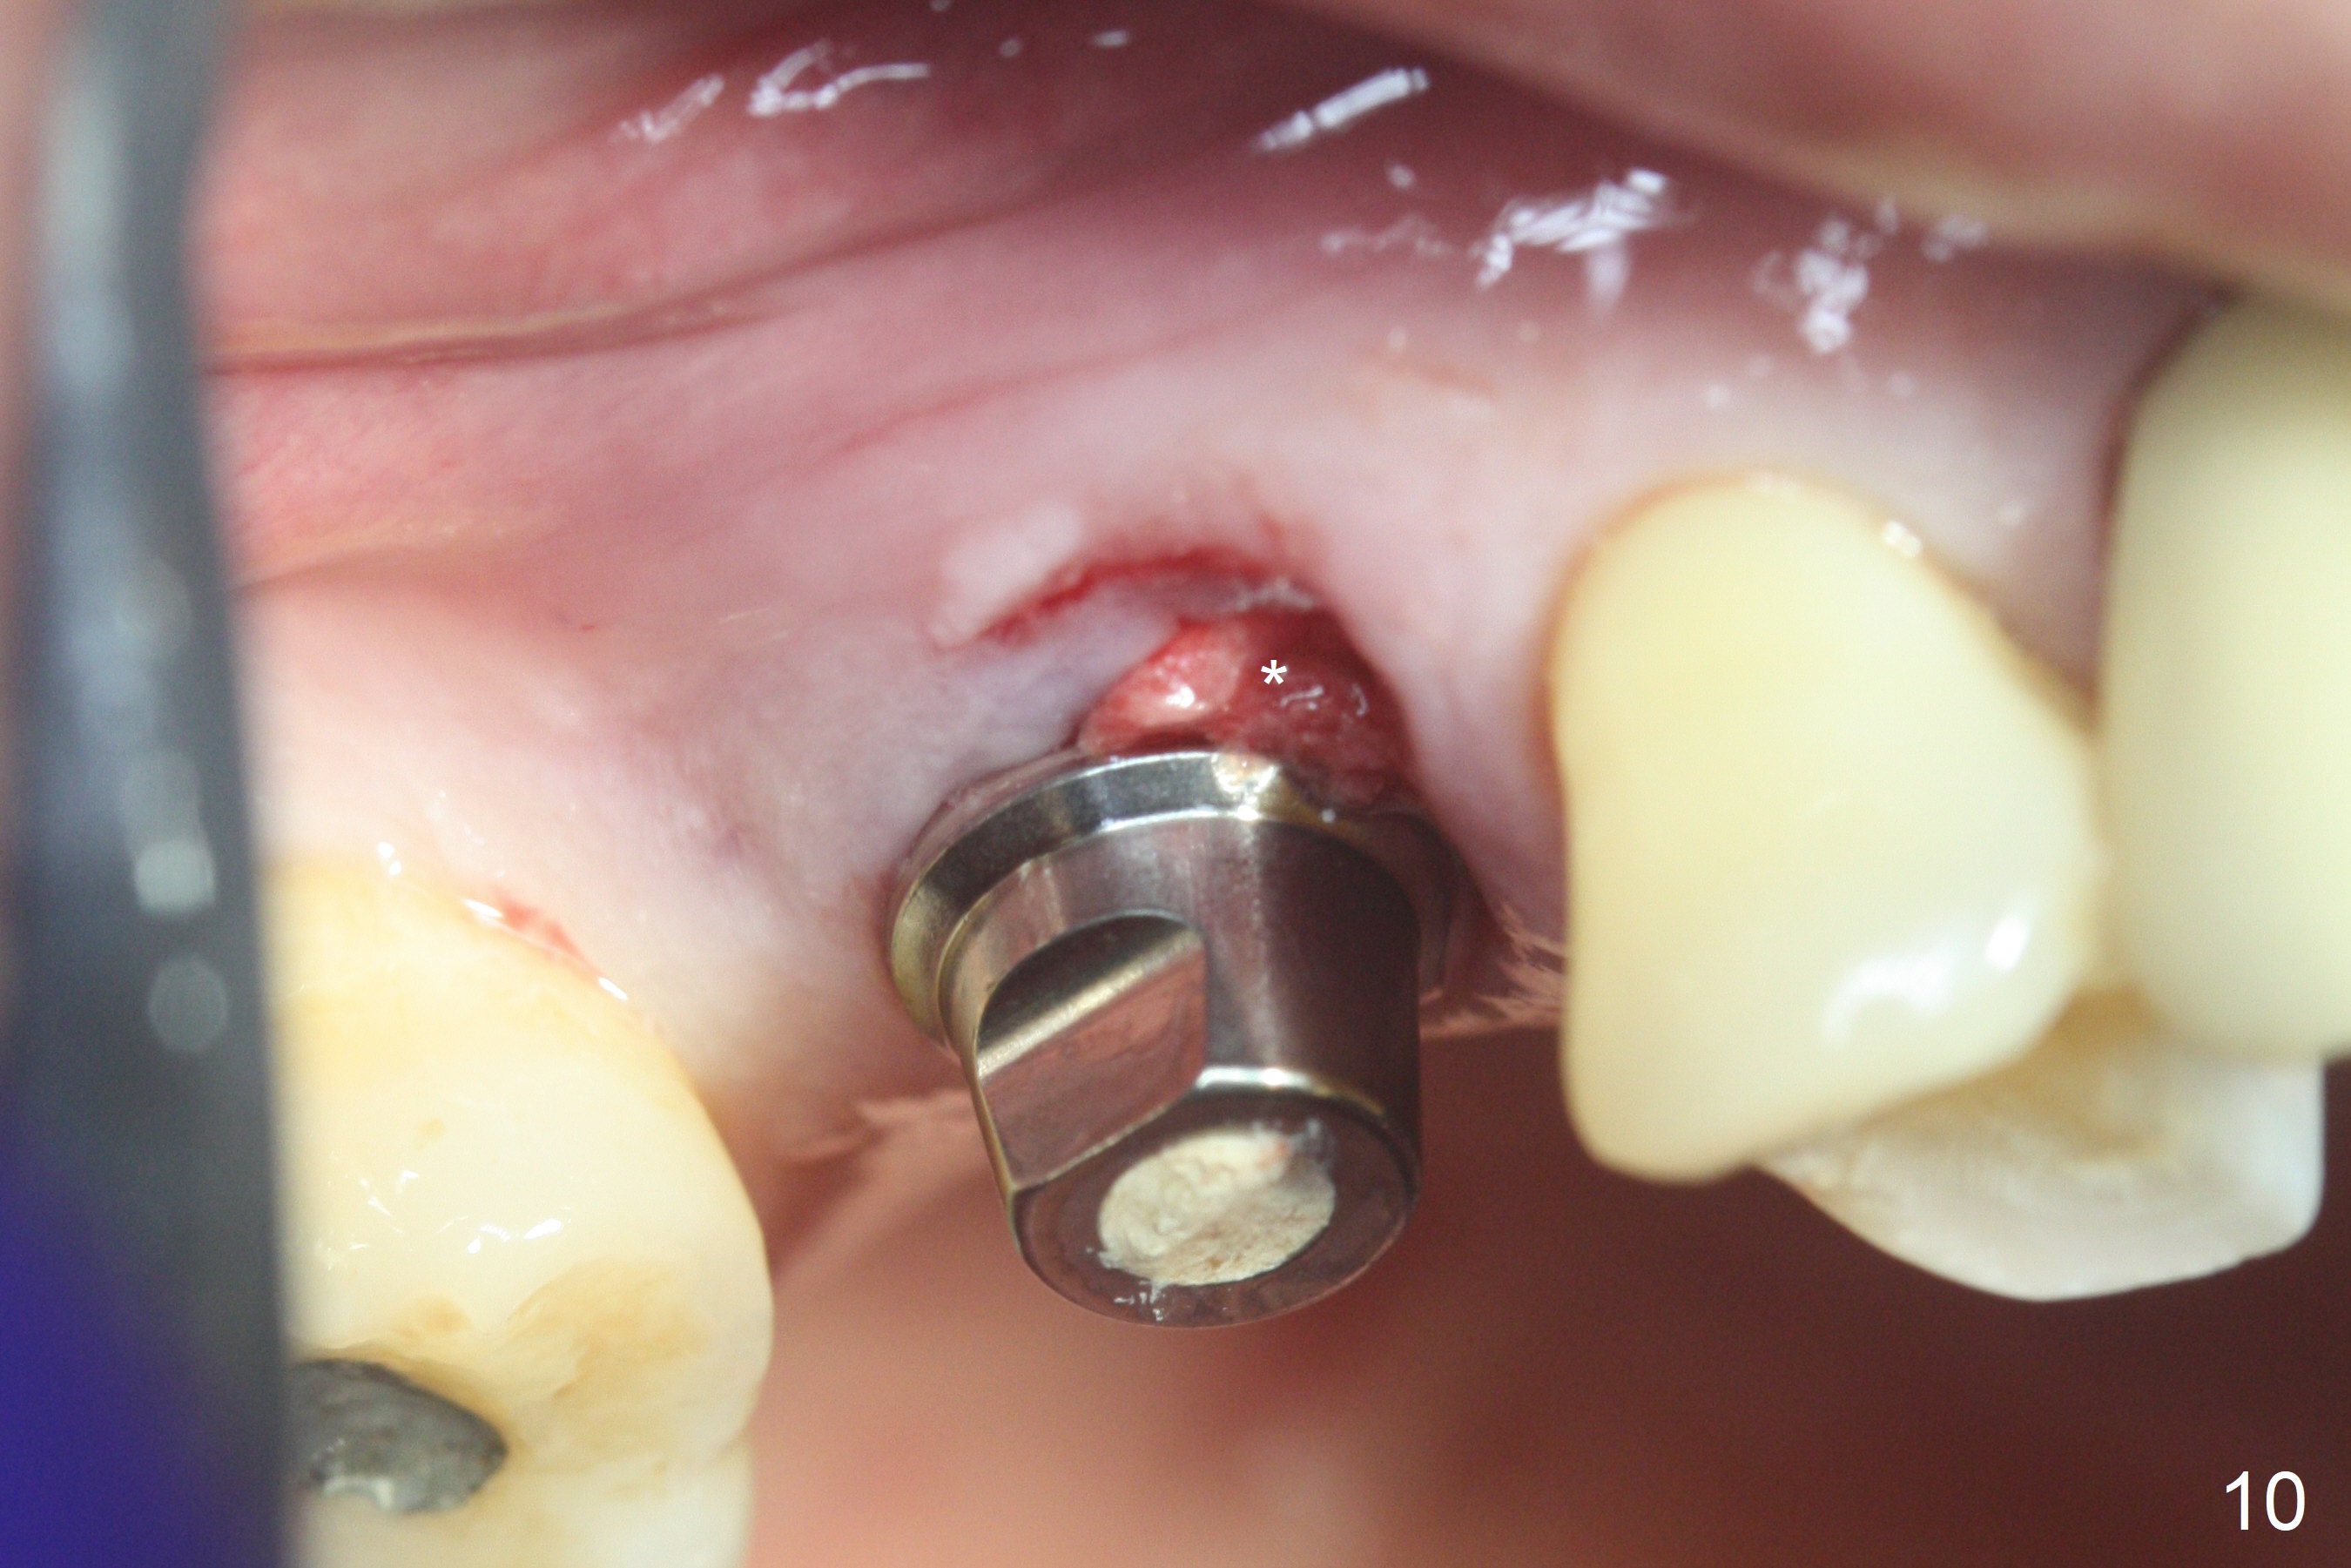

The palatal cusp of the affected 2nd premolar is apparently rotated distal (Fig.1). It is more obvious for the socket (Fig.2): the palatal (P) portion of the socket is more distal than the buccal (B) one. When the gauze is removed (Fig.3), Lindamann bur is used to remove the disto(D)palatal bone of the socket (data not shown), followed by starter drill in the DP wall obliquely (Fig.3'). Once the drill enters the bone for 1-2 mm, the bur is straightened and pushed slightly distal (Fig.3''). Fig.4 shows a parallel pin distal (overcorrect) to the original socket (Fig.4 red dashed line). Sequential osteotomy is conducted until 3.8x13 mm drill for 18 mm (Fig.5): note the 2 steps of the osteotomy (red lines). Since the apical portion of the osteotomy is larger than the drill, a larger implant than expected (5x16 mm) is placed. The implant ends up in the middle of the edentulous area (due to the stepped osteotomy; Fig.6-9; >60 Ncm). Vera allograft is placed (Fig.7-9 *) prior to and after placement of a 6.5x4(3) mm abutment (Fig.8-10). The remaining socket opening is sealed with a piece of Collagen plug (Fig.10 *). The socket is then closed by an immediate provisional (Fig.11 P). The abutment is retightened 2 months postop (Fig.12,13). The crown is cemented 4.5 months postop. Panoramic X-ray and CT are taken nearly 7 months post cementation (Fig.14,15) when the patient is ready for #30 implant guide preparation.